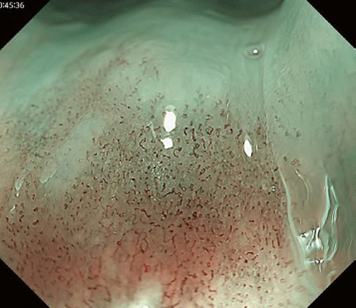

Predicting invasion depth of superficial esophageal squamous cell carcinoma is crucial in determining the precise indication for endoscopic resection (ER) because the rate of lymph node metastasis increases in proportion to the invasion depth of the carcinoma. Previous studies have shown a close relationship between microvascular patterns observed by magnifying endoscopy and invasion depth of the superficial carcinoma. Although there were two major classifications, Inoue and Arima, the Japan Esophageal Society (JES) integrated the two classifications and simplified it and developed a new magnifying endoscopic classification for the characterization and predicting invasion depth of superficial esophageal squamous cell carcinomas (SESCCs). This is essential for developing a treatment strategy for SESCC, in particular the indication for ER. Therefore, in this classification, morphological types of microvessels are classified into two categories of noncancerous [type A: normal epithelium, inflammation, and squamous intraepithelial neoplasia (SIN)] and cancerous (Type B: SCC) lesions. The cancerous types of microvessels corresponding to SESCCs are subclassified into three groups based upon an indication for ER as follows: an absolute indication type (Type B1: T1a-EP or T1a-LPM), a relative indication type [Type B2: T1a-MM or T1b-SM1(tumor invades the submucosa to a depth of 200 μm or less from the muscularis mucosa)], and a contraindication type [Type B3: T1b-SM2 (tumor invades the submucosa to a depth more than 200 μm)]. Diagnostic criteria of the JES classification are based on the degree of microvascular irregularity in the target lesion observed by magnifying endoscopy. Intrapapillary capillary loops (IPCL) are a basic unit of microvasculature in the stratified squamous epithelial layer. The microvascular irregularity is evaluated for the presence or absence of each of the following morphological factors: weaving (i.e., tortuosity), dilatation, irregular caliber, and different shape (i.e., various shapes). Microvessels are classified as type A if they have three or fewer factors (i.e., without severe abnormality; . Fig. 1a) and type B if they have all four (i.e., with severe abnormality). Type B is then subclassified into B1, B2, and B3 (. Fig. 1b–d, respectively) based on the running pattern or degree of dilatation of severely irregular microvessels. The definitions and schemas of type A and B vessels and predicted histology of invasion depth by type B vessels are summarized in . Table 1. A large scale validation study showed high overall accuracy (90.5%) of type B vessels of the JES classification. The most important auxiliary criterion in the JES classification is avascular area (AVA). AVA is defined as a low or no vascularity area surrounded by all subtypes of type B microvessels including B1 vessels. Diameters of AVA are positively correlated with sizes of histological cancer nest and the histological invasion depth of SESCC. Small (<0.5 mm), middle (0.5 ≤< 3 mm), and large (≤3 mm) AVA are suggestive of T1a-EP/ LPM, T1a-MM/T1b-SM1, and T1b-SM2, respectively. A key point to note is that any types of AVA (small, middle, and large) surrounded by B1 vessels are suggestive of T1a-EP or T1a-LPM SCC.